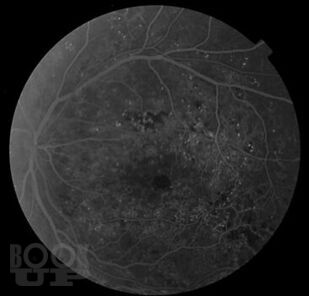

Диабетический макулярный отёк

Учебное пособие содержит информацию о диабетическом макулярном отеке. Большое внимание уделено патогенезу формирования отека в макулярной области и особенностям изменения сетчатки при сахарном диабете. Подробно рассмотрена современная классификация и основные методы диагностики диабетического макулярного отека. С современных позиций изложены основные подходы к лечению данных пациентов.